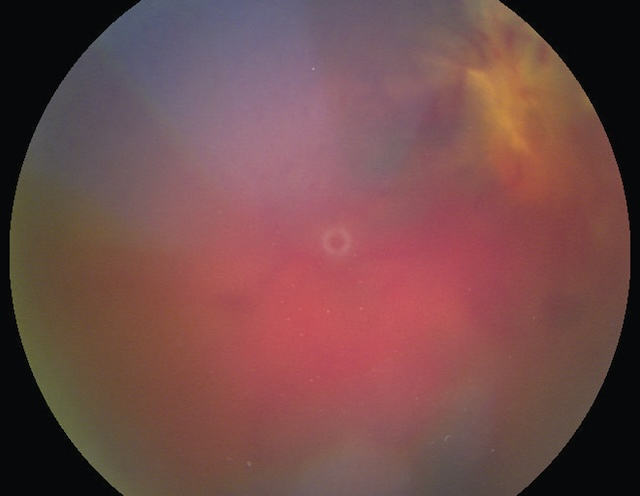

- • les hémorragies intravitréennes (fig. 1.38 et fig. 1.39);

Fig. 1.38 Hémorragie intravitréenne modérée, laissant voir la rétine. Cette photographie en fond d’œil obtenue par examen rétinien met en évidence une hémorragie intravitréenne modérée. Bien que le vitré soit envahi partiellement par du sang, les structures rétiniennes profondes restent en partie visibles, notamment la papille optique et le trajet de quelques vaisseaux rétiniens. La diffusion du sang est irrégulière, avec des zones plus denses parsemées de plages floues rouge foncé, traduisant la présence de sang diffus dans le vitré. L'ensemble du champ visuel apparaît voilé, mais sans obstruction totale, ce qui suggère un saignement de degré moyen. Ce type de présentation est souvent associé à une rétinopathie diabétique, une déchirure ou un décollement rétinien.

Fig. 1.39 Hémorragie intravitréenne massive. Cette vue de fond d’œil obtenue par imagerie rétinienne met en évidence une hémorragie intravitréenne massive, occupant l’ensemble de la cavité vitréenne et masquant les repères habituels comme les vaisseaux rétiniens, la papille ou la macula. La surface apparaît intensément saturée de tons rouges et violacés, avec une dominance hématique homogène au centre du champ. Une légère zone plus claire, circulaire et centrée, évoque un reliquat de transparence localisée, probablement au niveau de la fovéa. L’opacité globale du vitré rend impossible la visualisation nette des structures du pôle postérieur. Cette présentation suggère une rupture vasculaire sévère dans la cavité vitréenne, potentiellement associée à une pathologie vasculaire rétinienne ou à une complication post-traumatique. L’image traduit une obstruction dense de l’axe visuel, nécessitant une prise en charge urgente.